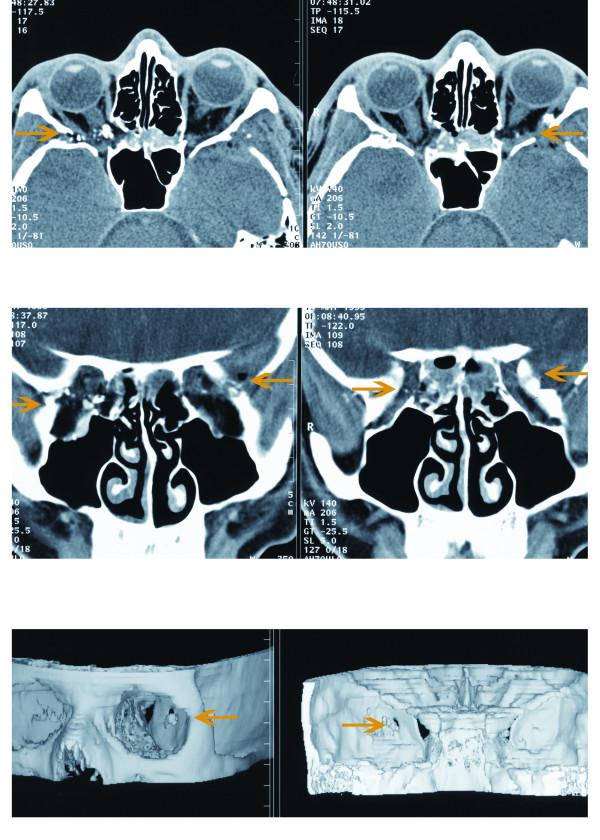

This is a report of a patient who developed macular holes from sclopetaria induced by indirect trauma. A 22-year-old male, suffered a gunshot wound that passed behind his eyes, resulting in bilateral macular hole formation

这是一位因间接性外伤导致 Sclopetaria 从而引发黄斑裂孔的患者报告。一位 22 岁男性,遭受枪击伤,子弹从眼部后方穿过,导致双眼黄斑裂孔形成